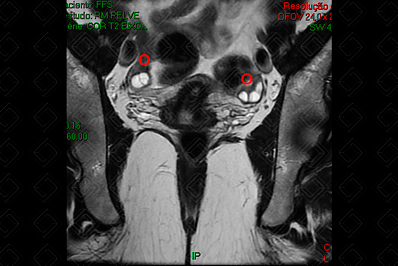

O protocolo básico da RM de pelve consiste em: T1 axial, T2 nos três planos (coronal, sagital e axial), T1 com saturação de gordura pré e T1 com saturação de gordura pós-contraste (Figuras 1, 2 e 3).

Texto alternativo para a imagem Figura 1. RM de pelve, ponderada em T2, plano coronal. Créditos: Dra. Elazir Mota - Rio de Janeiro/RJ

Texto alternativo para a imagem Figura 2. RM de pelve, ponderada em T2, plano coronal. Créditos: Dra. Elazir Mota - Rio de Janeiro/RJ

Legenda das siglas (Figuras 1 e 2): B = bexiga; O = ovários; U = útero.